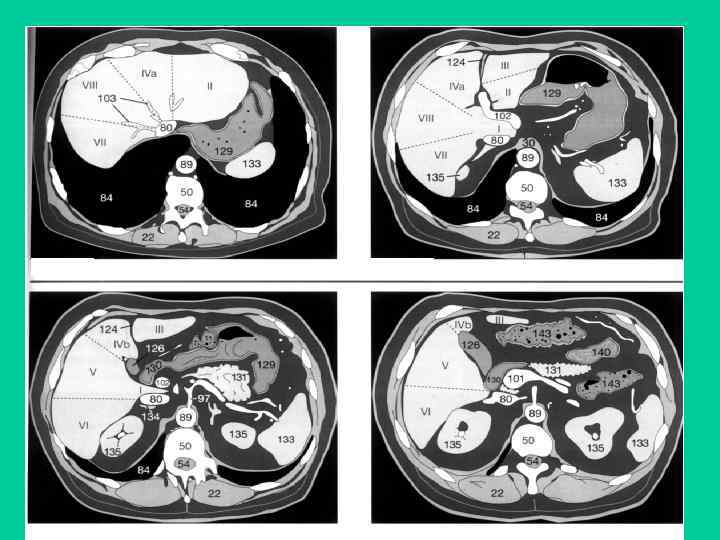

Аденокарцинома пищеводно-желудочного перехода и кардиального отдела желудка